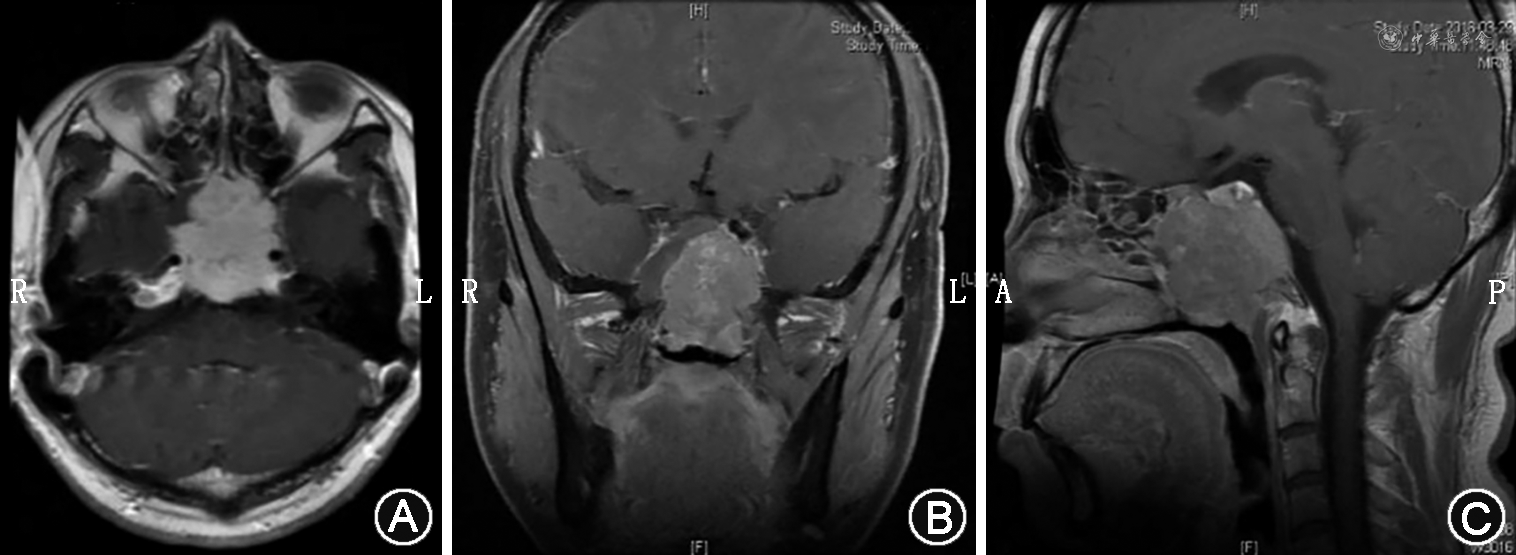

颈部淋巴结肿大是鼻咽癌患者常见的临床表现,局部淋巴结转移对于鼻咽癌患者的诊断、分期和治疗均具有重要意义(图2)。

鼻咽癌通常沿淋巴管引流通道逐级发生转移,一般不发生跳跃性转移。Ⅱ区淋巴结和咽后淋巴结通常是鼻咽癌最先累及的淋巴结,研究表明,Ⅱ区淋巴结和咽后淋巴结转移的发生率分别为71%和67%[24]。常见的转移顺序为:①自Ⅱ区向Ⅲ、Ⅳ区淋巴结转移;②自Ⅱ区向Ⅴ区淋巴结转移;③自咽后向Ⅴ区淋巴结转移。

鼻咽癌局部淋巴结转移具有如下特点[25]:①发生率高:首诊患者中局部淋巴结转移率高达80%;②双侧性:易出现双侧局部淋巴结转移;③通常由近及远沿淋巴管网逐级发生转移,跳跃转移发生率低;④较少累及Ⅰ区淋巴结;⑤局部淋巴结转移的发生率与患者的性别、年龄无明显相关性。

鼻咽癌颈部淋巴结转移的CT和MRI表现通常为[34, 35]:①Ⅰ~Ⅴ区淋巴结最小横径≥10 mm(Ⅱa区淋巴结为11 mm);②无论淋巴结大小,淋巴结中央区域出现液化坏死区或环形强化区;③1个区域内出现3个或3个以上的淋巴结相互融合,且其最小横径≥8 mm;④单个或融合淋巴结边缘不规则强化,其周围脂肪间隙模糊或消失。

咽后淋巴结位于咽后间隙,可分为内侧组和外侧组,内侧组位于椎前肌前方近中线部位,外侧组位于寰椎横突水平颈内动脉内侧[36]。咽后淋巴结转移与较低的远期生存率和较高的复发率有关[37]。MRI和CT检查对咽后淋巴结转移的诊断具有重要意义,通常表现为[38, 39]:①咽后淋巴结最小横径≥4 mm;②淋巴结内出现中心坏死、强化或包膜外侵犯;③内侧组出现可辨认的淋巴结。